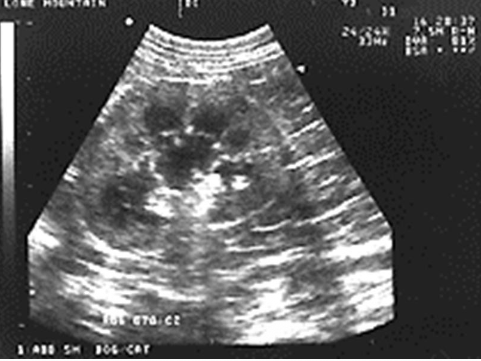

Kidneys

pelvis, cortex, and capsule are visible

adrenal glands are a dumbbell shape and are just cranial to the kidneys